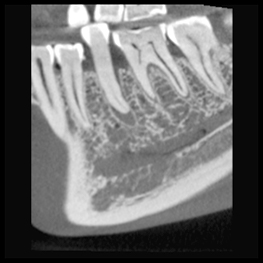

Höga upplösningar och standarddoser är inte alltid nödvändigt – ofta räcker det med lägre dos och upplösning. Planmeca Ultra Low Dose är tillräcklig för att se den mandibulära nervkanalen för implantatplanering och extraktion av visdomstand, till exempel. Allt kan göras med en otroligt låg dos.